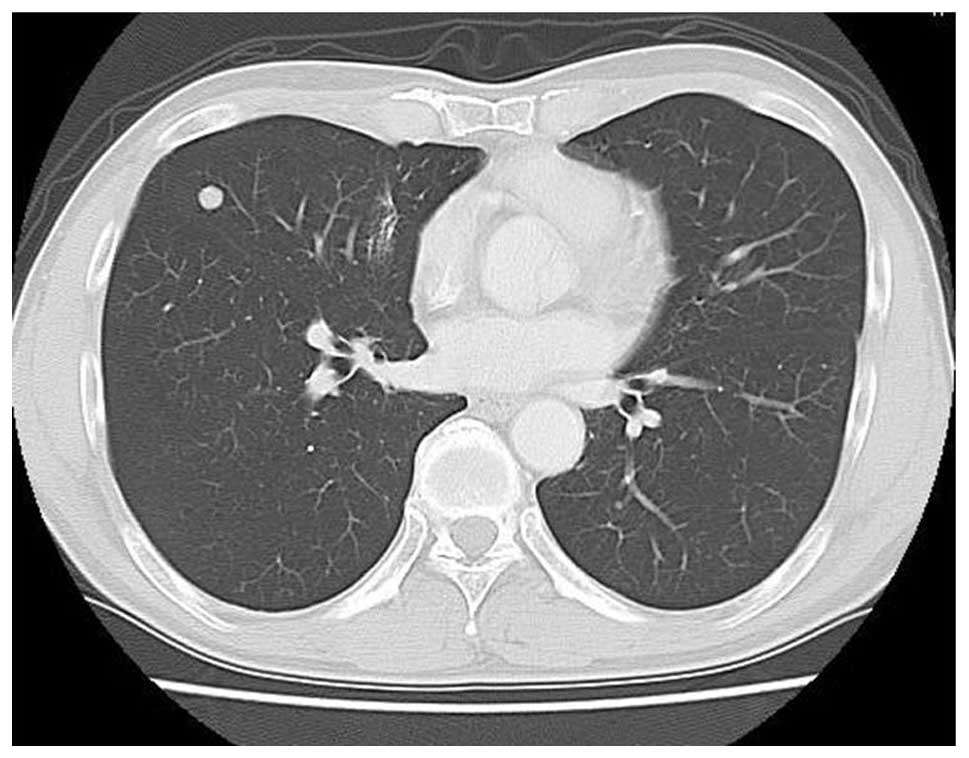

Figure 3

Lung computed tomography showing small nodules of lung metastases.

A 56-year-old male presented with a mass in the right facial bone that had been apparent for three months, and dysesthesia, which had occurred gradually at this site. The patient incidentally identified the tumor and visited Wakakusa-Daiichi Hospital, Higashi-Osaka (Osaka, Japan), where the mass was confirmed with computed tomography (CT) examination. Nothing of note was found in the patient’s past medical and family histories, and the findings from the routine laboratory studies were within the normal limits. Plain X-rays showed no particular findings, but regional CT showed a soft-tissue mass with prominent ossification in the central region, and involving the parapharyngeal space (Fig. 1), in which the anterior septum ballooned owing to compression from the mass. Magnetic resonance imaging (MRI) revealed heterogeneously low intensity to isointensity results on T1-weighted sequences and low to moderately high intensity results on T2-weighted images, with a size of 5.6×4.8 cm (Fig. 2). Lung CT revealed multiple small nodules that were suspected to be lung metastases (Fig. 3).